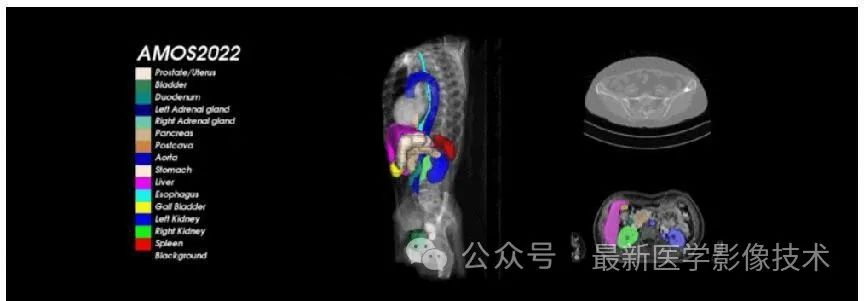

一、AMOS2022介绍

AMOS2022挑战赛是一种大规模、临床和多样化的腹部多器官分割基准。它提供了从多中心、多供应商、多模式、多阶段、多疾病患者收集的 500例 CT 和 100 例MRI ,每一例都有15个腹部器官的体素级注释。

AMOS2022数据集示例说明,提供了 500 例 CT 和 100 例MRI 以及 15 个腹部器官的体素级别注释, 包括脾脏、右肾、左肾、胆囊、食道、肝脏、胃、主动脉、下腹部腔静脉、胰腺、右肾上腺、左肾上腺、十二指肠、膀胱、前列腺/子宫。请注意,某些数据点由于生理移除或由于未扫描身体部位而丢失了某些器官。